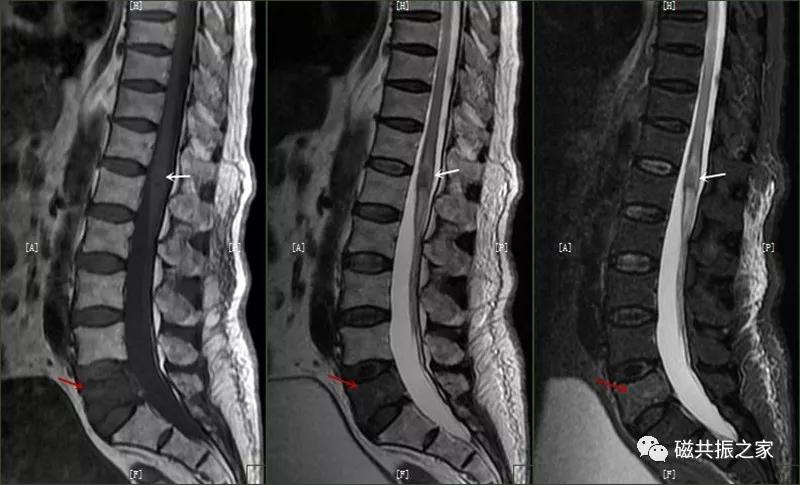

椎体压缩性骨折常成前窄后宽的楔形改变,新鲜骨折(红箭头)常在T1WI呈低信号(出血时可呈高信号),T2WI呈低、中信号,在脂肪抑制的T2WI上呈高信号。椎体陈旧性骨折(白箭头)信号类似于正常椎体信号。如需了解脊柱骨折分型请查阅脊柱骨折的分型。